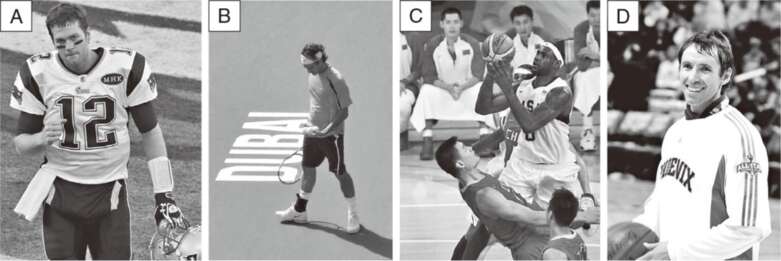

站在內分泌的角度,我通常會談兩大類荷爾蒙,一個是皮質醇,另一個是褪黑激素,對我們的睡眠最重要。透過右頁這張圖,我們可以看出它們兩個本身就有自己的日週期,而起伏的步調是不同的。

我在《真原醫》和《靜坐》等其他作品也談過皮質醇,又稱「壓力荷爾蒙」(stress hormone)。你應該也可能記得,身體有一個很完整的神經系統,我們通常會稱為自律神經系統,它本身是獨立運作,調控許多生理功能,例如消化、心跳、呼吸、視力的調整、肌肉的收縮放鬆、排洩等等。自律神經系統又可以再細分成兩個子系統,也就是我常說的交感和副交感神經系統。

其中,交感神經系統是幫助我們面對生存的考驗,讓肌肉收縮,呼吸和心跳加快……隨著一天開始,我們要面對種種的事,身體的交感神經系統也就啟動了。交感神經的活化,讓我們加強每一個部位的機能,活力變高,代謝加快。同時,讓我們覺得自己是清醒的。清醒的程度,是在早上10點達到高峰,而反應速度則是在下午3點達到最佳表現。

我們早上一醒來,血壓慢慢地開始上升,讓我們更容易從床上爬起來,面對一整天的事。而皮質醇其實一大早就開始釋放,一路上升,最高峰的時間,當然每個人不同,但差不多在早上8點到10點之間。這是為了增加血糖,讓我們得到行動所需要的能量。

我們很多人喜歡在下班的時候運動,不光是那個時候有時間,身體也比較舒暢。心血管的效率和肌肉的力量,都在下午五點左右達到最佳的狀態。也就是說,尤其是對運動員,傍晚才是體能最好的時段。這一點,再加上時差,你大概沒想到,對美國的職業運動員影響相當大。無論籃球或橄欖球,遇到全國性的聯賽,有主場優勢和時差優勢的隊伍,可以在自己體能最好的時候開賽,勝率當然會比較高1。

只要常常出差的人,都知道在北美,隨時可以買到褪黑激素。一般人在飛機上,就會先吞一顆,幫助自己在飛機上睡一覺,以及接下來調整時差。

褪黑激素可以說剛好和皮質醇作用的時間相反,是在太陽下山後,9點開始分泌,夜裡11〜12點到高峰,到天亮時,已經幾乎消失。其實,褪黑激素的水平和我們的體溫變化趨勢是剛好相反的。到了夜晚,褪黑激素上升,而核心體溫逐漸下降,身體的作用程序也開始慢了下來。也就是說,我們要入睡,無論內分泌和全身的生理與代謝程序,都要同步朝向睡眠的方向前進。

光是這一點,其實也帶來一個很重要的工具。失眠的人,首先要懂得把環境的溫度降低。在睡眠中,核心體溫會自然降下來。如果環境溫度高,身體無法散熱,體溫降不下來,當然也就幹擾睡眠。